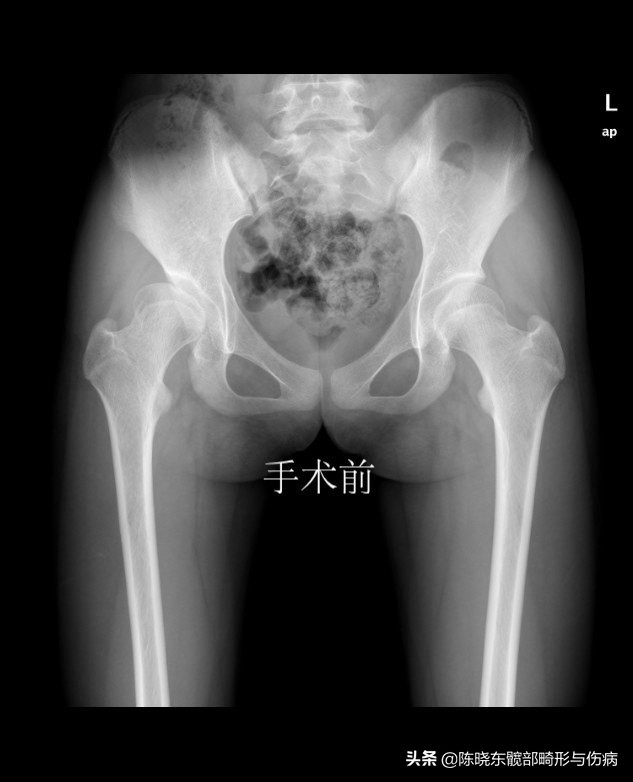

上图为23 岁青年女性,右侧腹股沟疼痛半年,曾经当作滑膜炎治疗三个月无效。来我院行髋臼周围截骨术,术后看见髋臼对股骨头的覆盖包容明显改善,疼痛消失,恢复正常的生活/学习/娱乐。

而髋臼发育不良患者的髋臼和股骨头片子就没有办法完全匹配,一部分或大部分的股骨头可能暴露在髋臼之外。若大部分股骨头脱离了髋臼,会有明显的长短腿。行走、运动时,股骨头会直接和髋臼发生摩擦,导致疼痛。多数患者是在20岁—40岁出现症状,男女比例为1:8。如果没有得到及时治疗,生活、工作会受影响,还可能导致骨性关节炎、股骨头坏死等,最后不得不导致换人工关节。

全脱位就是股骨头完全脱到了髋臼的外面,患侧的腿明显要短。半脱位的话,仍有一部分股骨头包容在髋臼里,患者的两条腿长短没有区别。应该说,全脱位比较容易早期发现,一眼就能看出来。半脱位的话,很多时候是等到髋部疼痛难忍了,患者才会到医院检查。